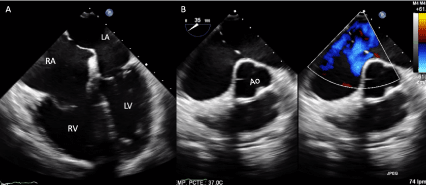

Figure 1. Two-dimensional transesophageal echocardiogram at 0º (A) and 35º with color Doppler (B), with a multi-hole ostium secundum atrial septal defect and dilation of the right cavities. Abbreviations: RA-right atrium; RV-right ventricle, LA-left atrium, LV-left ventricle, Ao-aorta

The patient was sent to our institution to continue with the diagnostic studies. At cardiac examination with arrhythmic heart sounds, splitting of the second sound and systolic murmur in the second right intercostal space. The laboratories showed hemoglobin (16 gr/dl) and hematocrit (49%) both within normal parameters. The electrocardiogram (ECG) with heart rate of 89 bpm, atrial fibrillation, and incomplete right bundle branch block. Chest x-ray showed cardiomegaly. The TTE demonstrated ASD with Qp / Qs of 1.9 and dilation of right cavities. Two and three-dimensional transesophageal echocardiogram (TEE) confirmed the presence of a multi-hole ostium secundum ASD, with the presence of at least five defects of different sizes (Figures 1, 2, videos 1 and 2). Right heart catheterization showed mild pulmonary hypertension with pulmonary systolic pressure of 48 mmHg. The patient was no candidate for percutaneous treatment due to the size of the multi-hole ostium secundum ASD and is currently awaiting surgical treatment.